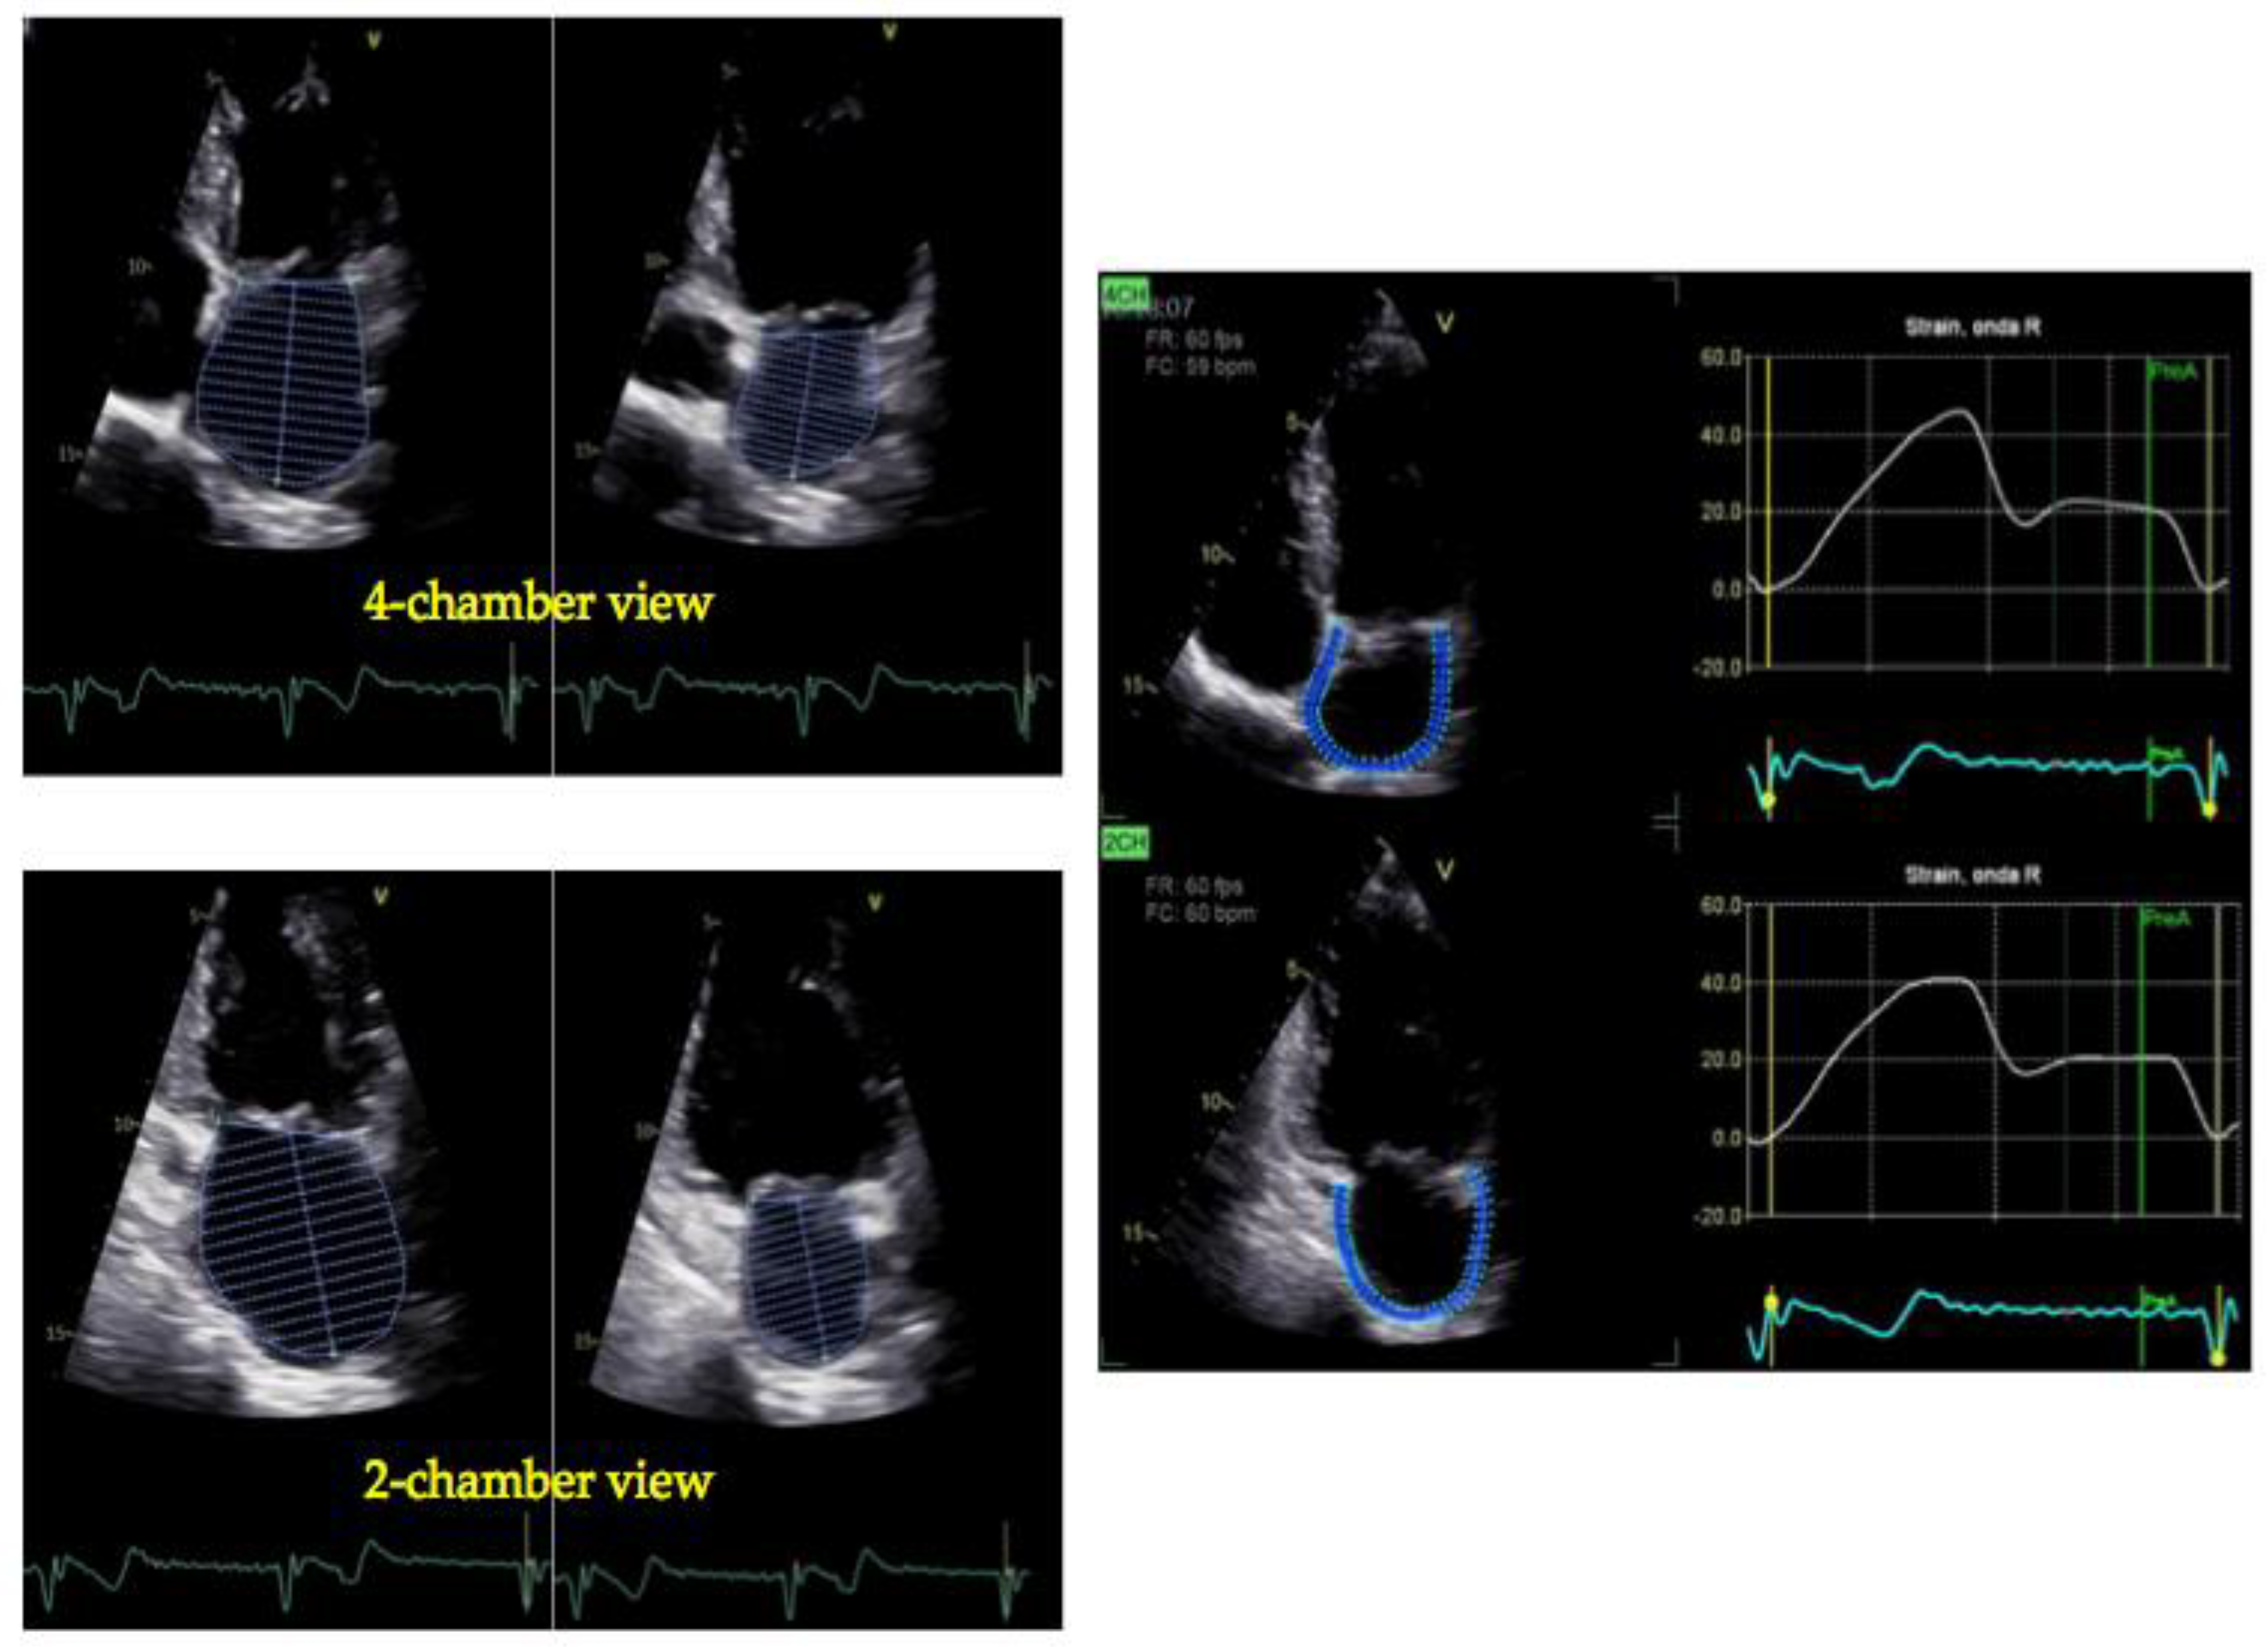

4. Peak Atrial Longitudinal Strain

5. Tissue Doppler Imaging and LA Function: A Simplified, Complementary Approach